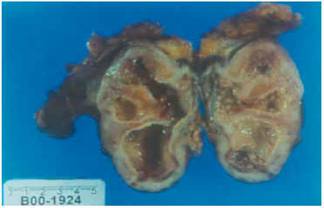

Afectiune renala cronica caracterizata prin prezenta, timp indelungat, a germenilor microbieni la nivelul parenchimului renal, determinand inflamatia tesutului renal cu afectarea concomitenta a tubilor renali si producerea de leziuni secundare glomerulare.

Pieolnefrita cronica

TABLOUL CLINIC:

Pielonefita cronica se poate manifesta sub forma unor atacuri repetate de pielonefrita acuta sau doar prin simptome generale, nespesifice: fatigabilitate, cefalee, scadere ponderala, astenie; o parte din bolnavi au simptomatologie clinica de afectare renala: febra frisone, dureri lombare, polachidisurie, insotite eventual de bacteriurie; uneori se constata hipaetensiune arteriala; foarte rar poate exista edem.